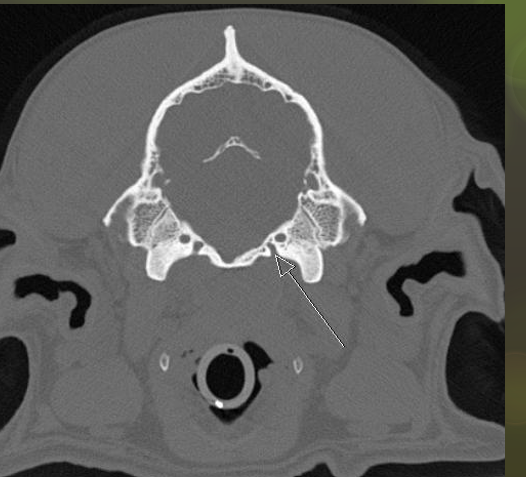

jugular foramen